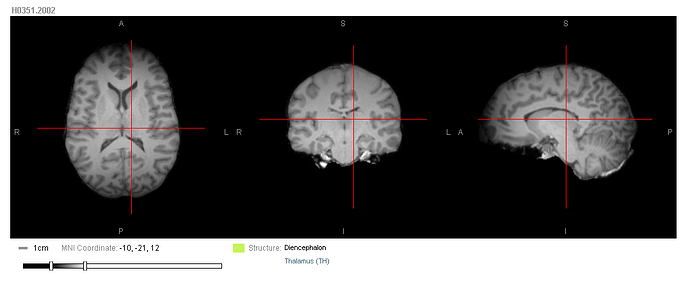

T1-weighted MPRAGE scans were acquired for the postmortem brains using 3T Siemens Trio MR scanners (TI=900ms, TR=1900ms, TE=3.03ms, 9 degree flip angle, 1mm isotropic voxels). Scans were performed in cranio for some brains and ex cranio for others. See the Microarray whitepapers for more specific scan sequence details for each brain.

All T1 images were registered to MNI space. FreeSurfer’s affine registration was used for the in cranio scans. For ex cranio brains, the T1 was first rigidly aligned using FSL (Jenkinson, et. al, 2002) and then non-rigidly aligned using ANTS (Avants, et. al., 2011). The 3-D affine transform from a location in the MR volume to MNI space is encapsulated in the Alignment3d model.